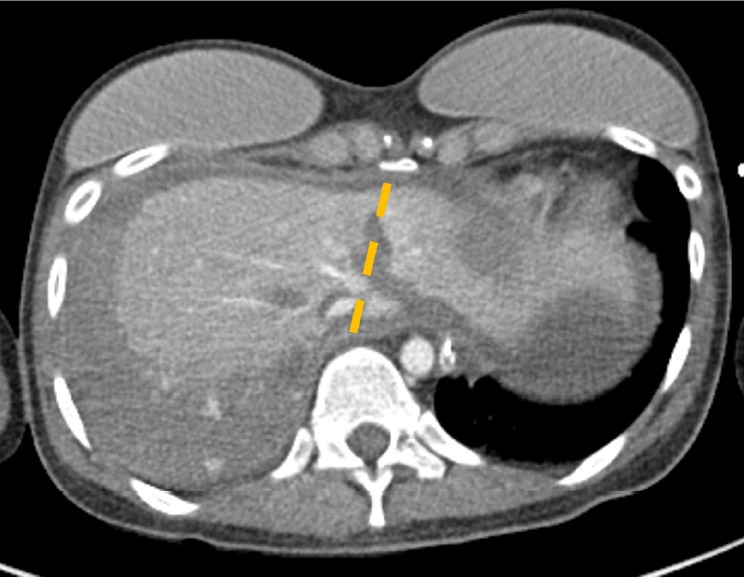

Cardiac compression is the most crucial component of successful cardiopulmonary resuscitation (CPR). However, CPR procedure poses a risk of complications, even when CPR providers perform cardiac compressions as recommended. Reports indicate that solid organ injuries, including liver injuries, occur with an incidence of about 0.6% to 3%. In this particular case, a 25-year-old woman was found hanged in her apartment. She was transported to a nearby hospital where CPR was administered for approximately 30 minutes until she was resuscitated. Subsequently, an abdomen-pelvis computed tomography scan revealed a liver injury. The location of the liver injury, between the sternum and spine, suggested it was a compression injury caused by CPR. There was no evidence of extravasation or active bleeding; thus, conservative management was chosen for the liver injury. By hospital day 4, the patient's pupil reflex had completely disappeared. Electroencephalography showed generalized attenuation, indicating severe global brain damage. Liver injury is a relatively rare post-CPR complication, with an incidence of 0.6% according to a retrospective analysis of a cardiac arrest registry. The liver is partially situated between the sternum and spine. The end of the sternum is shaped like an inverted triangle, resembling a sword. Therefore, if the CPR provider's hands are placed too low or excessive pressure is applied, the sternum can injure the left liver. Blood loss from liver injuries could potentially hinder the successful resuscitation of patients. In this case, had there been no blood loss from the liver injury, the patient might have maintained better cerebral perfusion and function.